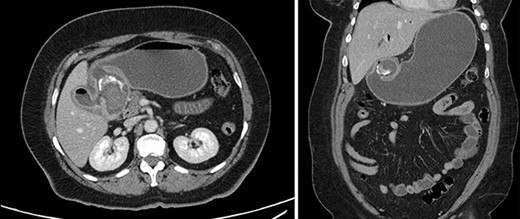

Contrast-enhanced CT. Axial and coronal views of a 4 cm stone in the duodenal bulb, gastric dilation, and pneumobilia in the operative patient.

A 63-year-old woman with morbid obesity, hypertension and gastritis presented to the emergency department with 2 days of diffuse epigastric pain, nausea and coffee ground emesis. Before onset of these symptoms, the patient described an 8-month history of vague abdominal pain. She was afebrile and hemodynamically stable. Her abdomen was tender to palpation in the epigastrium and right upper quadrant, with no peritoneal signs. Labs were significant for leukocytosis to 17.4 k/μL, lactate to 2.2 mmol/L and Hgb to 10.0 g/dL. All other labs were within normal limits. Abdominal CT demonstrated gallbladder wall thickening, mucosal hyperenhancement and calcified stones within the gallbladder. There was also a 4 cm stone in the duodenal bulb, gastric dilation and pneumobilia. The distended and inflamed gallbladder was inseparable from both the distal stomach and proximal duodenum (Fig. 3).